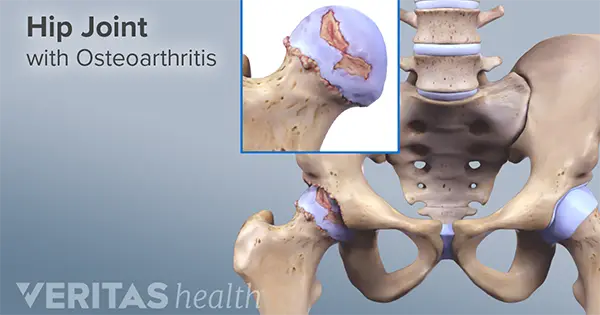

ارتروز مفصل ران

آرتروز لگن همان ساییدگی مفصل ران است که به آن استئوآرتریت هم میگویند و در این بیماری غضروف مفصل ران به دلایل متنوع از بین میرود و باعث شروع درد لگن میگردد ….